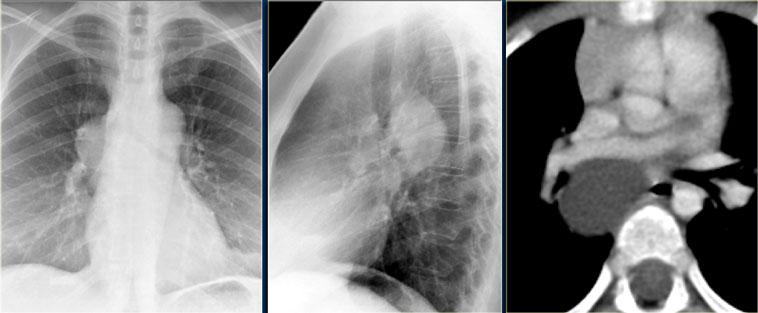

U nguyên bào thần kinh thường có hình thoi, tỷ trọng mô mềm; 50% các khối u lồng ngực có vôi hóa.

U nguyên bào thần kinh phát triển qua nhiều khoang liên sườn và thường xâm lấn ống sống.

Các hình ảnh CT cho thấy một khối vôi hóa ở trung thất sau trải dài qua nhiều đốt sống, xâm lấn vào ống sống.

Trên các hình ảnh MRI, sự xâm lấn vào ống sống được thể hiện rõ hơn (các mũi tên).